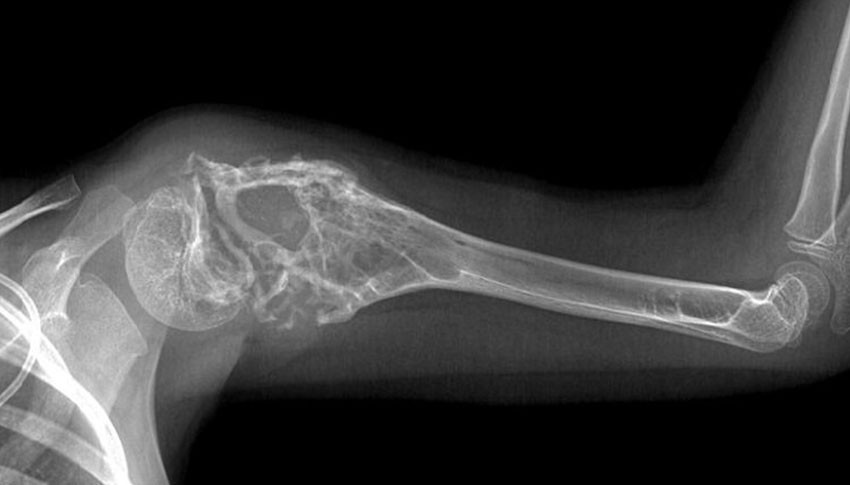

Операции при раке костей конечностей

Если злокачественная опухоль растет из костей рук или ног, то у врача есть два варианта хирургического лечения:

ампутация конечности;

удаление опухоли с сохранением конечности.

Каждый подход имеет свои преимущества и недостатки. В итоге решение принимается совместно с пациентом с учетом всех плюсов и минусов. Большинство людей стремятся сохранить конечность. При этом стоит понимать, что подобные операции более сложные, имеют повышенный риск осложнений.

Ампутация снижает трудоспособность и влияет на качество жизни. Но такое лечение рака костей более простое, надежное, реже дает осложнения и рецидивы.

Если конечность сохранена, часто приходится удалять не только кость, но также мышцы, нервы, сосуды. Всё это требует последующего эндопротезирования и длительной реабилитации. Вместо собственной кости устанавливают искусственную (из металла или других материалов). Иногда приходится ставить также искусственный сустав. Это влечет за собой риск осложнений, с которыми пациент должен быть ознакомлен. Иногда встречается инфицирование эндопротеза или его асептическое расшатывание. Кроме того, в будущем могут потребоваться операции по замене искусственной кости или сустава.

Тем не менее, операции при раке кости с сохранением конечности хоть и являются более сложными, но используются чаще. После них требуется реабилитация от 3 до 12 месяцев. В противном случае сохраненная конечность может остаться нефункциональной и человек не сможет восстановить трудоспособность.